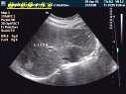

男,23岁,发现肝脏内有一个增强回声,结合超声声像图,提示最可能是?(?)A.海绵状血管瘤B.肝癌C.肝囊肿D.脓肿E.肝腺瘤

问题 男,23岁,发现肝脏内有一个增强回声,结合超声声像图,提示最可能是?(?)

选项 A.海绵状血管瘤 B.肝癌 C.肝囊肿 D.脓肿 E.肝腺瘤

答案 A